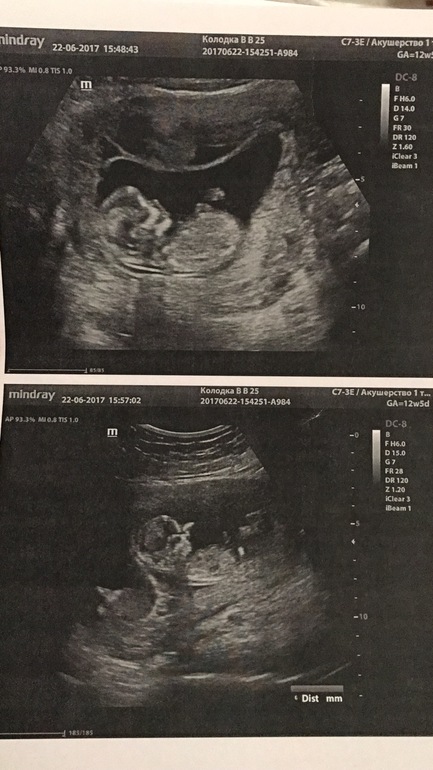

Узи первого триместра форум

Узи первого триместра форум 117 фото